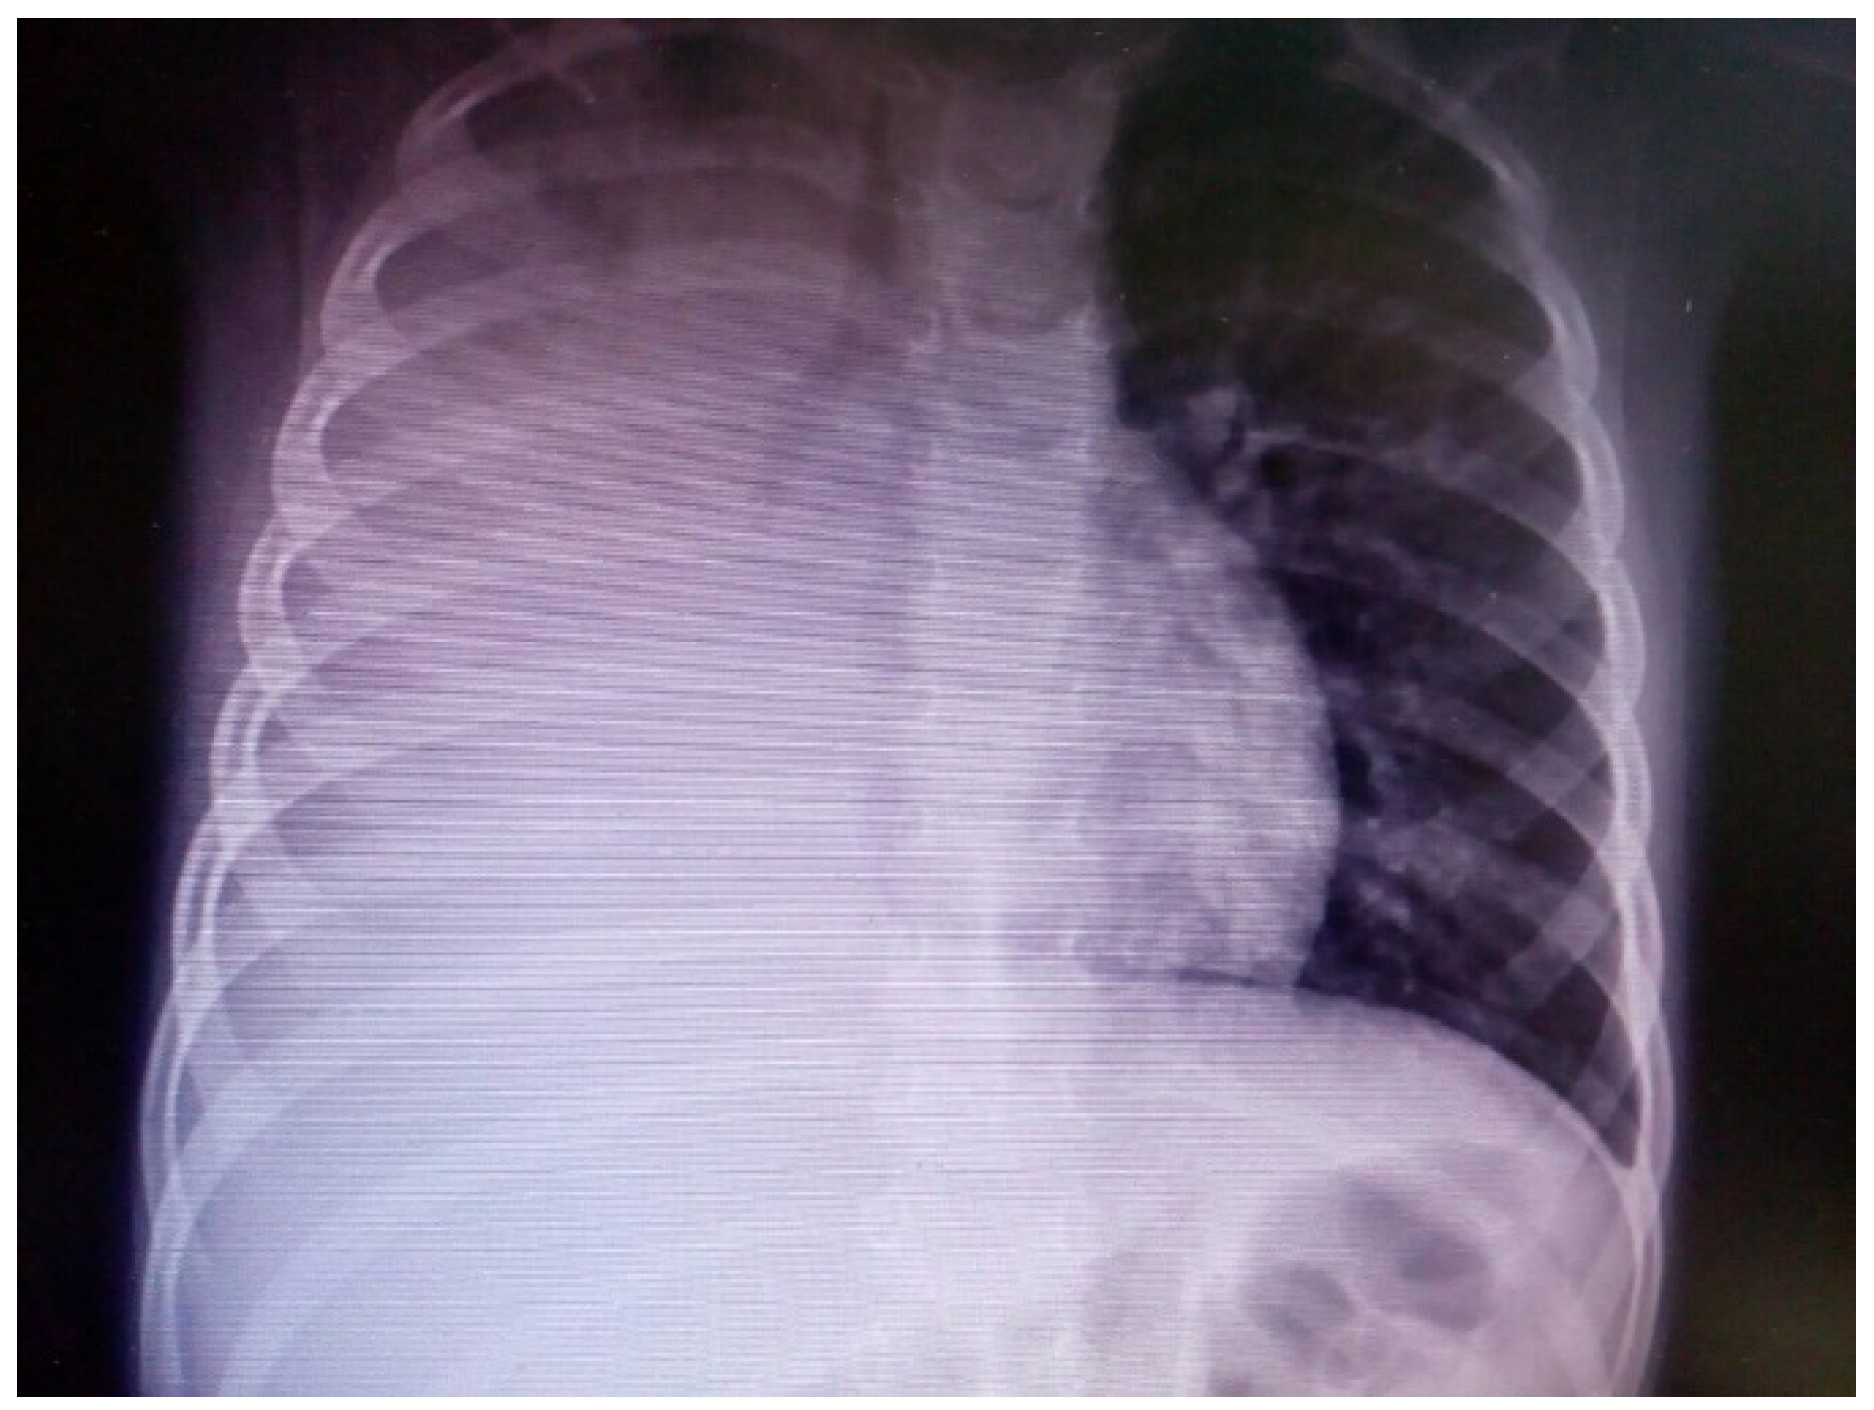

- Quick admission, processing, and basic tests, such as blood tests and chest X-ray;